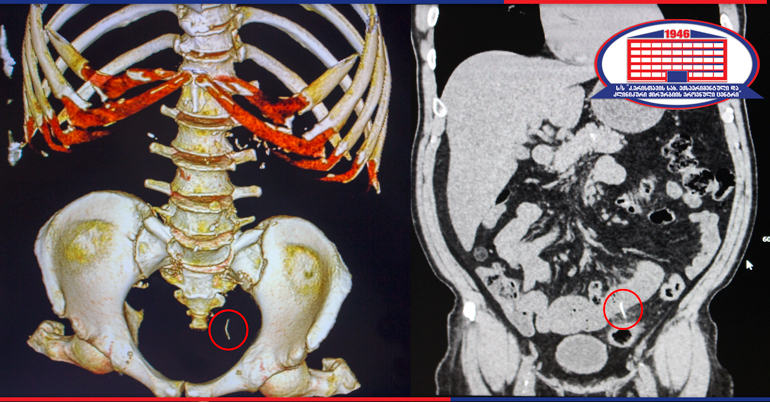

The radiologist of the clinic, Irakli Gigiadze noted that the small intestine was damaged by a foreign body. An unknown foreign body emanated from the intestine into the abdominal cavity. The patient underwent laparoscopy. A foreign body was found and removed, and the damaged area of the small intestine was sutured.

The foreign body that had been removed from the patient's small intestine was a metal wire (the part of the wire scourer Cleaner), the size of which was 4 cm and had got into the gastrointestinal tract with the consumption of food.